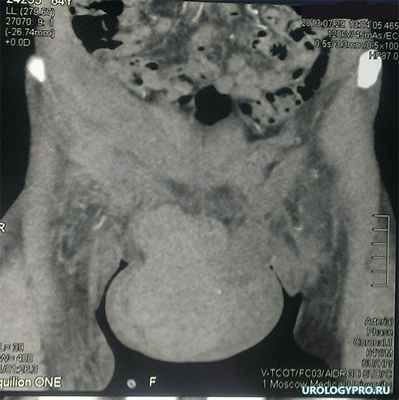

Больной Г. 65 лет, 12 августа 2013 года - падение на металлическую балку с высоты собственного роста. В связи с невозможностью самостоятельного мочеиспускания в этот же день выполнена пункционная цистостомия. В послеоперационном периоде отмечен выраженный отек мошонки, при УЗИ и МСКТ (рис 1) установлена гематома тканей промежности с распространением на правую половину мошонки.

Рис 1. компьютерня томограмма. КТ-картина гематомы мошонки общим объемом 300 мл.